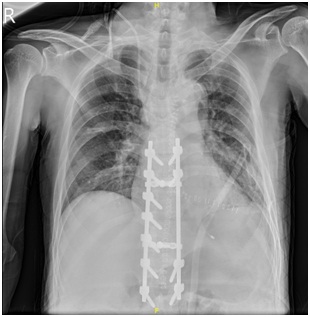

病例一术后内固定情况